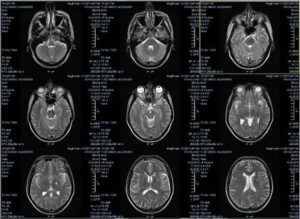

- Магнитный резонансный томограф передает на специальный компьютер результаты обследования. Они отображаются в виде снимков головного мозга. В идеале должно быть 4 проекции: передняя, верхняя, левая и правая.

МРТ головы помогает получить снимки, на которых ткани обозначены затемнениями и просветлениями. Ткани мозга имеют серый цвет. Протекающие церебральные жидкости отображаются в виде ручейков светло-серого оттенка. Черные полости на изображении — это внутримозговые синусы.

Если все области головного мозга развиты правильно, то интенсивность сигнала, полученного от томографа, будет одинаковой. У здорового человека желудочковая система должна иметь нормальные размеры.

Любое ее расширение или уменьшение считается отклонением. В норме должно быть и периваскулярное, и субарахноидальное пространство. Обращают внимание на состояние борозд и извилин.

В них не должно быть никаких отклонений.

Структура самого мозга также должна находиться в пределах нормы. Он не должен быть смещен. Нормальный размер должны иметь глазницы, слуховые проходы и носовые пазухи. В мозговых тканях не должно наблюдаться никаких диффузных или очаговых изменений.